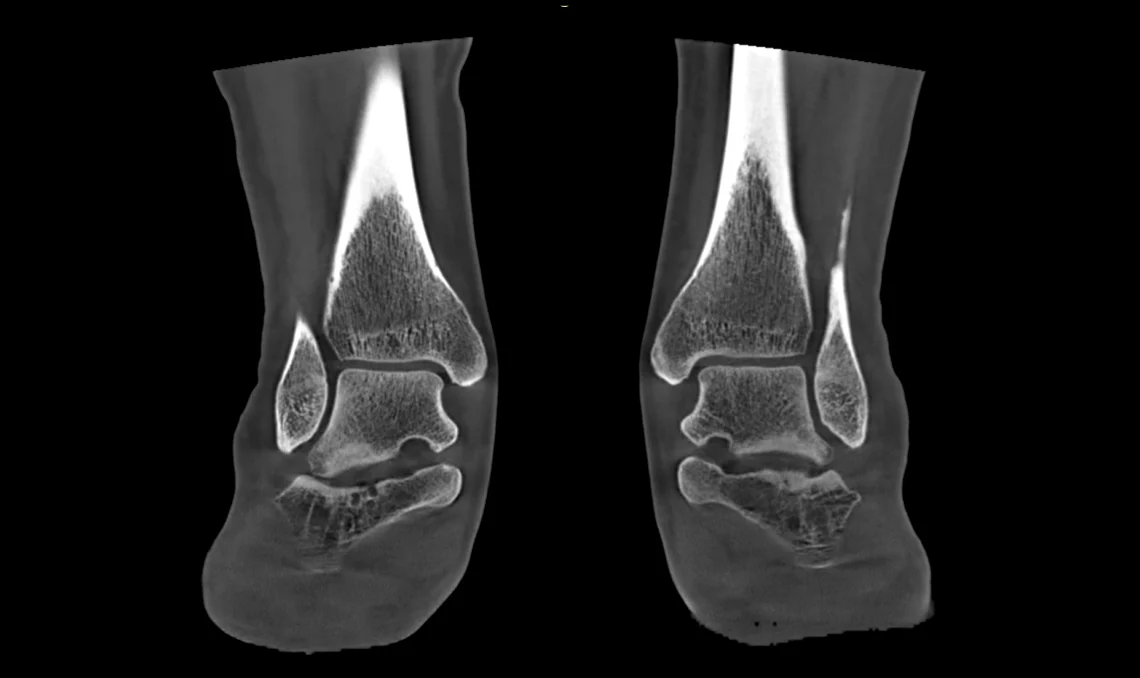

Le scanner CBCT Planmed XFI se distingue par une large ouverture de 85 cm et un champ de vision généreux, autorisant l’exploration du corps entier aussi bien en position allongée (décubitus) qu’en position debout (en charge). Son grand détecteur plan et sa source de rayons X haute puissance effectuent une rotation complète à 360° autour de la zone examinée, capturant rapidement des images anatomiques 3D détaillées.

Le système délivre des images 3D en ultra-haute résolution pouvant atteindre 75 microns, garantissant une qualité d’image exceptionnelle, une grande finesse de détail et une précision diagnostique optimale.